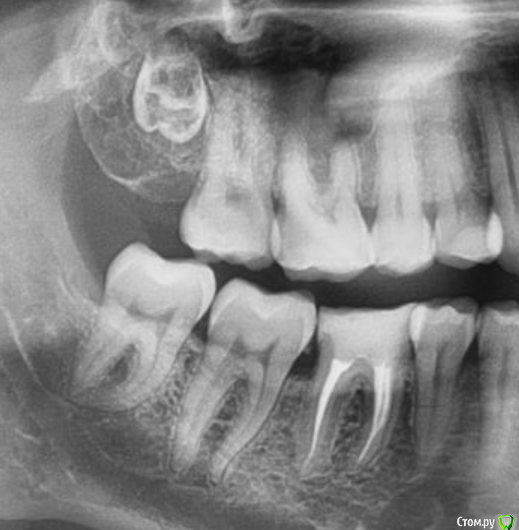

SkyWay Опубликовано 13 июля, 2020 Поделиться Опубликовано 13 июля, 2020 Добрый день.Задумался в 30 лет ставить брекеты, хотя в интернете есть разные мнения, особенно часто говорят, что не стоит в таком возрасте выпрямлять прикус, из-за того что зубы потом разъедутся, но и не мало, что никогда не поздно. В общем сам вопрос, все зубы на месте, но из 4 зубов мудрости, один так и не вырос.Вот как он выглядит: Будут ли что делать с этим зубом в случае установки брекет системы? или нет смысла его трогать? Ссылка на комментарий

SkyWay Опубликовано 17 июля, 2020 Автор Поделиться Опубликовано 17 июля, 2020 На консультации ортодонт сказал удалить все 8ки, в том числе и этот ретированый.Хирург по снимку сказал, что он вроде даже не вырос, и чтобы его удалить его надо высверливать, и разнести полчелюсти..Вот теперь ещё менее понятно что делать Ссылка на комментарий